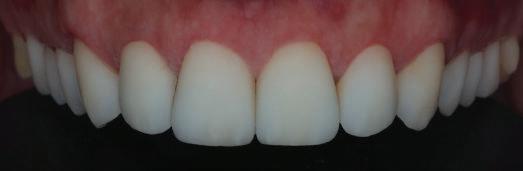

планта бе поставена временна коронка (фиг. 10 и 11), докато бъде изготвена окончателна та. Бе постигнат отличен кра ен резултат. Меките тъка ни около импланта напълно заздравяха, което доприне се за перфектната хармония между бяла и розова естетика (фиг. 12–15).

Dental Tribune Bulgarian Edition / октомври 2022 г.18 воначалния план. Тези пробле ми бяха адресирани чрез допъл нителна поръчка на алайнери с торк контрол и зададено екст рудиране на задните зъби с цел установяване на добри оклузал ни контакти в дисталните об ласти, като бяха предвидени и оптимизирани атачмънти с контрол над корените за корекция на ангулацията на макси ларните резци (фиг. 8). Резултати от лечението Панорамната рентгено графия след ортодонтското лечение показа благоприятна паралелна позиция на съседни те зъби, подходяща за поставя не на имплант в областта на #22, както и конвергенция на ко рените на зъби #44 и 45 (фиг. 9), но преценихме, че няма да от деляме допълнително лечебно време за коригирането ѝ поради факта, че пациентката бе мно го доволна от постигнатия до момента резултат. След при ключване на лечението бяха постигнати отлични взаимо отношения клас I при мола рите и канините, а срединни

съвпадаха. Върху им

(LFH: 56.5 mm) и размерите на меките тъка ни останаха непроменени. На клонът на горните резци бе за пазен (Ui–FH: 115.8°), а долните резци бяха леко наклонени ве стибуларно (Li–APog: 30°; фиг. 16). ДИСКУСИЯ Липсата на зародиш на по стоянен горен латерален резец е налице при 3.5–6.5% от евро пеидната раса, като при жени е по-честа, отколкото при мъ жете в съотношение 3:2.8–10 Възможни са няколко лечебни подхода, включително замя ната му с преоформен канин, отваряне на място чрез орто донтско лечение и протетич но възстановяване, както и ав тотрансплантация. Устано вено е, че изборът за затваря не на място или за отваряне то му все още подлежи на дис кусия сред ортодонти и проте зисти.11,12 Според литературните дан ни затварянето на простран ството и замяната на липсва щия латерал с канин се предпо чита в случаи на едностранна липса на зародиш, балансиран профил, кучешки зъби и премола ри със сходна форма и цвят, дву челюстна протрузия или клас II малоклузия.13–15 Отваряне на пространство по-често се изби ра при клас I, наличие на диасте ми и треми в горната зъбна дъга или голяма разлика в размерите на канини и премолари.16 Скорошно проучване е уста новило, че изборът на лечение при конгенитално липсващ ла терал е пряко свързан със след ните фактори17: възрастта на пациента при започване на лечението; индивидуалните особености при всеки конкретен случай; и сътрудничеството между специалистите в лекуващия екип. Макар да има проучвания, фа воритизиращи леченията със затваряне на място11,18, всеки случай трябва да бъде оценяван индивидуално. В презентирания в тази статия случай бе взето решение за отваряне на мяс то и протетично възстановя ване, понеже целта бе да се по стигнат клас I отношения при канините и моларите, както и по-широка усмивка. За да се из бегнат компромиси, след лече нието бе постигнат клас I при моларите и кучешките зъби, несъответствието по Болтън бе подобрено и срединната ли ния бе коригирана. Други изслед вания демонстрират отлични естетични и функционални ре зултати при лечение с отваря не на място и протетична ре хабилитация.19 И двете лечеб ни модалности са подходящи за третиране на вродена лип са на зародиш на латерал и да ват сходни функционални и па родонтални резултати20, като при едно проучване

но

между членовете на екипа и пациента. ЗАКЛЮЧЕНИЕ Случаите на липсващи лате рални резци трябва да бъдат третирани от перспектива та на интердисциплинарна ди агностика и лечение. Употреба та на софтуера ClinCheck има доказани предимства за плани ране, комуникация между кли ницистите и пациента и фи нализиране на лечебния план, като се адресират всички же лания и притеснения на паци ента. Настоящият доклад на клиничен случай доказва, че с помощта на съвременните ме тоди един успешен екип от спе циалисти (ортодонт, консерва тивен зъболекар и хирург) може да се стреми към отлични ре зултати и да постига есте тични и функционални усмив ки без компромиси. Ред. бел.: Статията Treatment of a patient with a congenitally missing lateral incisor using aligners: A case report е пуб ликувана за първи път в сп. aligners–international magazine of aligner orthodontics, бр. 1, издание 1/2022. Библиографията е налична при издателя. За авторите: Д-р Iro Eleftheriadi завършва дентална медицина в Атинския университет, а магистратурата си по медицинска статистика – през 2014 г. в Публичния университет в Атина, Гърция. Специализира ортодонтия и завършва през 2017 г. в Университета в Тел Авив, Израел. Предстои ѝ да защити докторан тура във Факултета по дентална медицина към Университета в Атина, Гърция. Д-р Christodoulos Laspos завършва дентална медицина през 1995 г. в Атинския университет, Гърция, а магистратурата си завършва през 1999 г. във Фа култета по дентална медицина към Университета в Тенеси, Мемфис, САЩ. Печели стипендия и специализира лечение на пациенти с лицево-челюстни малформации в Университета в Тексас, Далас, САЩ, и е сертифициран специалист от Европейския борд на ортодонтите. Той е докторант в Универ ситета в Берн, Швейцария. От 2000 г. д-р Laspos практикува в частната си ортодонтска практика в Лимасол, Кипър. Той е основател и директор на MEDICLEFT, Кипърски център за цепки и лицево-челюстни аномалии, както и директор на фондацията Synergy, която осигурява следдипломно обучение на лекари по дентална медицина. Научен съ трудник е във Факултета по дентална медицина към Европейския университет в Кипър. Д-р Laspos изнася лекции по цял свят по теми като лицево-челюстни мал формации, ортогнатна хирургия, мултидисциплинарен подход и нови технологии в ортодонтията. Той е активен член на Европейското общество на Енгел и прези дент на Европейското ортодонтско общество. Фиг. 12а–c Финални странични (а и c) и фронтална интраорални снимки (b). Фиг. 13а и b Финални оклузални снимки. Фиг. 14 Финална снимка на усмивката отблизо. Фиг. 15 Финална екстраорална снимка на усмивката. Фиг. 16 Финална телерентгенография и цефалометричен анализ. Фиг. 12a Фиг. 13a Фиг. 14 Фиг. 15 Фиг. 16 Фиг. 13b Фиг. 12b Фиг. 12c клиничен случай с алайнери